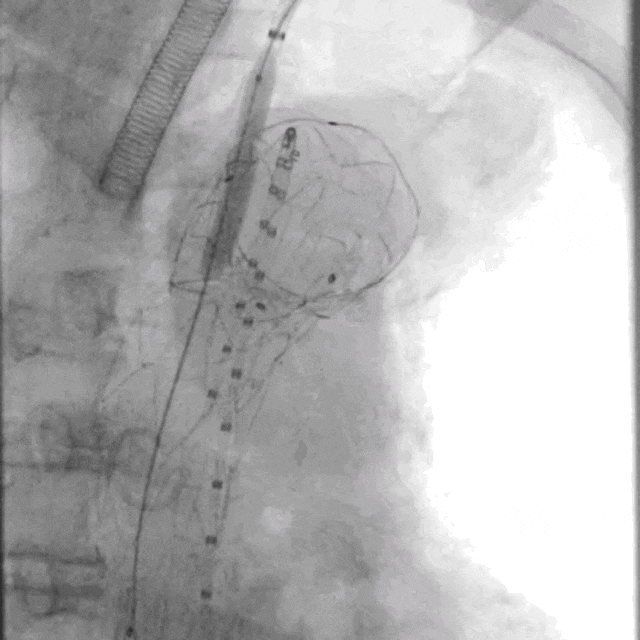

术前造影LAO

2.右股动脉置鞘交换Lunderquist导丝后,经右侧股动脉上华脉泰科PTBS3834180胸主动脉覆膜支架至左颈总动脉后缘位置,完全覆盖病变段,释放支架。

近端定位LCCA根部后缘

释放大支架

释放近端裸支架